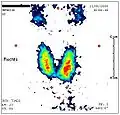

Normalisierung nach Therapie.

Normalisierung nach Therapie.